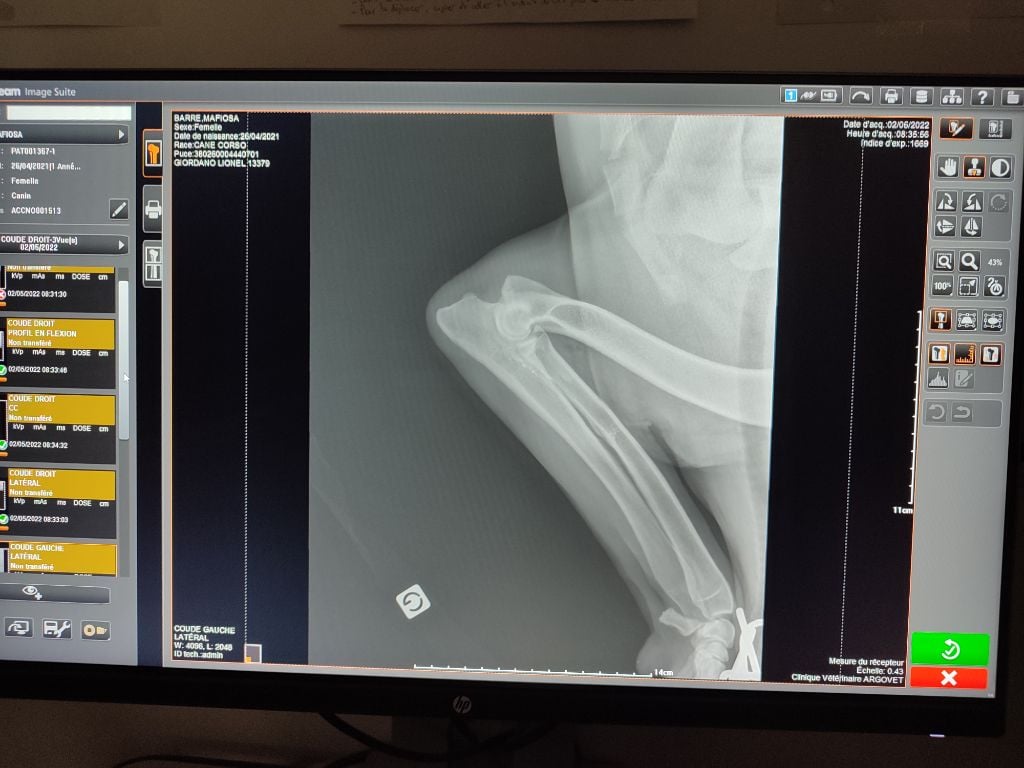

| Couleur | noire ADN HD C / ED 0/ DSRA N/N |